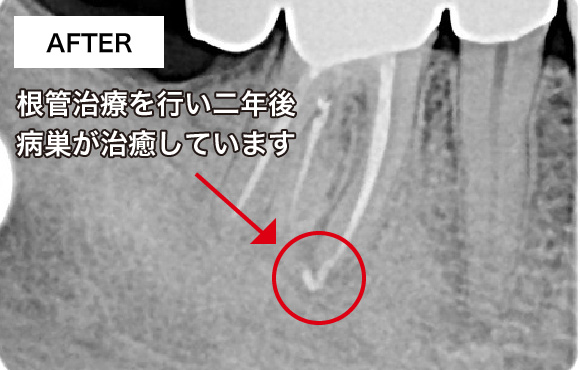

根管治療BEFORE・AFTER

確認のためレントゲンを撮ります。